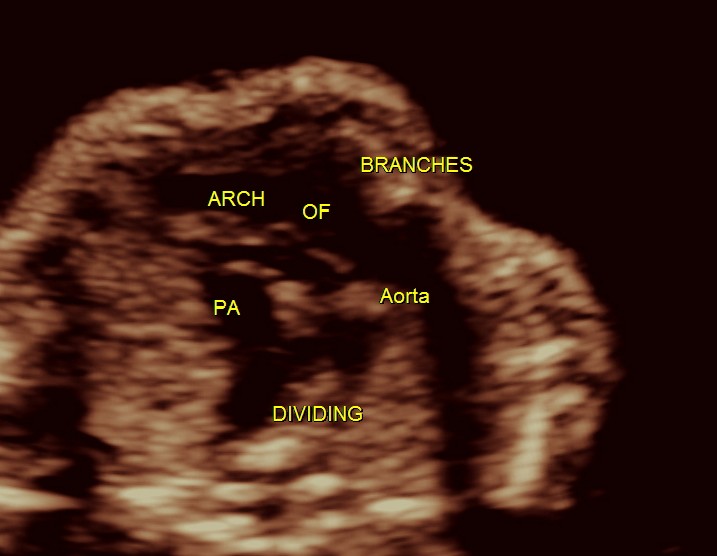

3 vessel view shows a prominent single vessel , which is very suggestive of outflow tract anomalies like transposition of great arteries, double outlet right ventricle , truncus arteriosus and corrected transposition of great arteries.

another view of the above two

Under normal circumstances the chamber in front of descending aorta is left atrium ; and the aorta arises from the left ventricle which has no trabeculations ; the pumonary artery which divides into the two branches arises from the anterior right ventricle and crosses over the aorta .

here we can see the pulmonary artery with its two branches arising from the lower (left) ventricle .and the aorta arising from the anterior (right ) ventricle.

pulmonary artery dividing into two